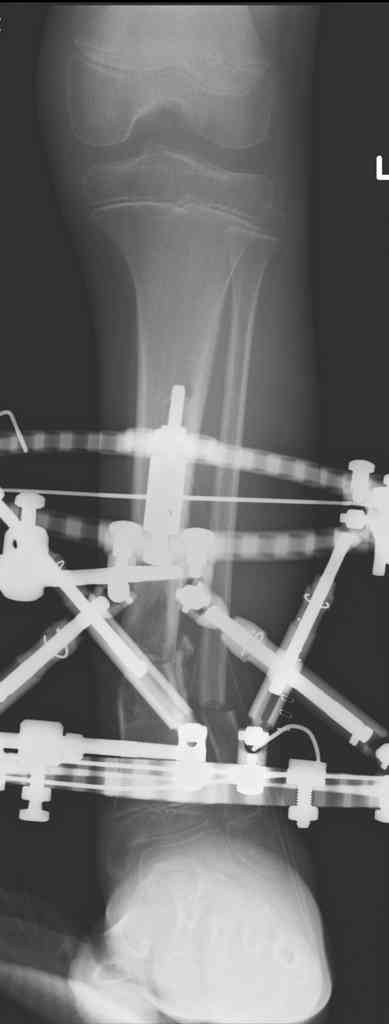

5. Ну и чтобы не быть голословным. Молодой человек подорвался на фугасе (Чечня, 2005 год). Свежие рентгенограммы:

Соответственно ожоги и дефект мягких тканей, переломы костей стопы и пр. Наложили аппарат

Илизарова (как придется), хирургически обработали и героически заживляли мягкие ткани с многочисленными кожными пластиками. В итоге через полгода я принял его вот таким:

Реализовал описанную выше методику, и в итоге вот что получилось. Высылаю лишь прямые проекции,

в боковых тоже всё в тему.

Очень пригодились карбоновые кольца (Джолдас -огромное спасибо, я твой должник!!!), поскольку остеопороз дистального отломка был просто невероятный. На цифровом рентгене с трудом угадывались контуры.

Рентген в процессе перемещения - внизу карбоновые кольца, тракция фрагмента спицами с упором.

внешний вид в аппарате - не завершающем этапе, сначала стопа тоже была фиксирована в аппарате.

Сейчас аппарат сняли, но случай ещё не завершенный.

Признаюсь честно, не совсем уверен в прочности консолидации на стыке косточек. Кроме того, укорочение в районе 6 см. Сейчас реабилитация - ходит опираясь на ногу с одним костылем.

Продолжение, видимо, будет... Возможно, будем удлинять.